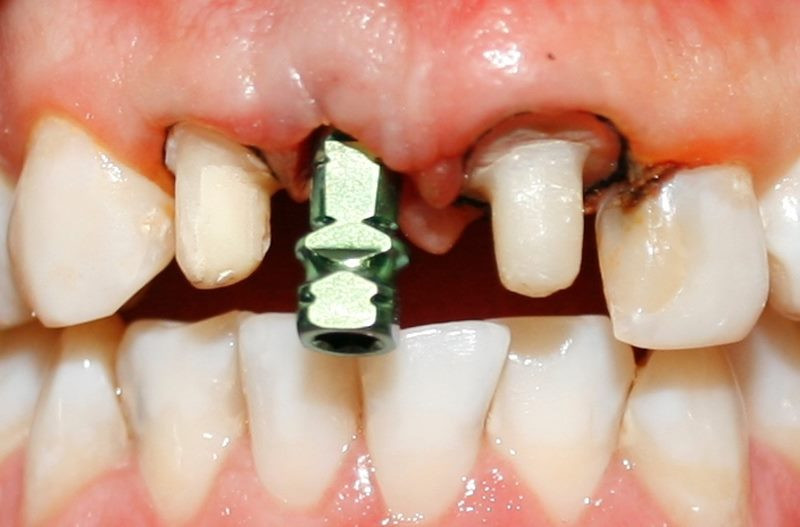

Vista clínica implante

Implante colocado en incisivo central derecho